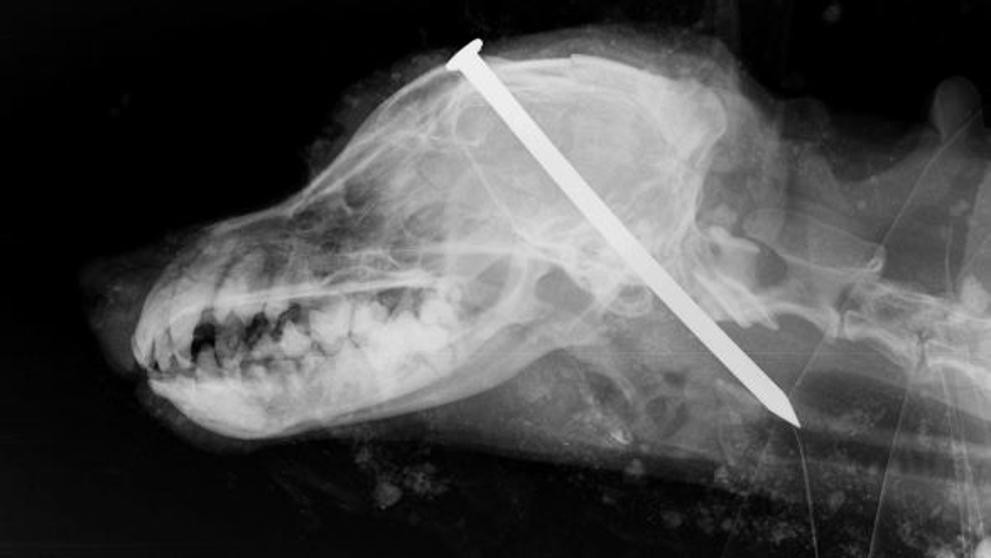

Un grave caso de crueldad animal se vivió en Yorkshire del Norte, en el Reino Unido, donde hallaron un perro enterrado vivo con un clavo entre los ojos.

Sin embargo, los especialistas no pudieron hacer nada para poner fin al dolor que el perro estaba padeciendo y debieron sacrificarlo, según el diario GazetteLive .

La Real Sociedad para la Prevención de la Crueldad Animal decidió publicar fotografías explícitas para denunciar lo ocurrido y reclamar que se encuentre a los responsables.